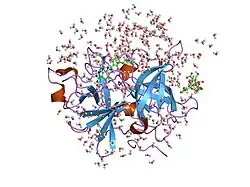

Urokinase is a 411-residue protein, consisting of three domains: the serine protease domain (consisting of residues 159–411), the kringle domain (consisting of residues 50-131), and the EGF-like domain (consisting of residues 1-49). The kringle domain and the serine protease domain are connected by an interdomain linker or connecting peptide (consisting of residues 132–158). Urokinase is synthesized as a zymogen form (prourokinase or single-chain urokinase), and is activated by proteolytic cleavage between Lys158 and Ile159. The two resulting chains are kept together by a disulfide bond between Cys148 and Cys279.[9]

The most important inhibitors of urokinase are the serpins plasminogen activator inhibitor-1 (PAI-1) and plasminogen activator inhibitor-2 (PAI-2), which inhibit the protease activity irreversibly. In the extracellular matrix, urokinase is tethered to the cell membrane by its interaction to the urokinase receptor.